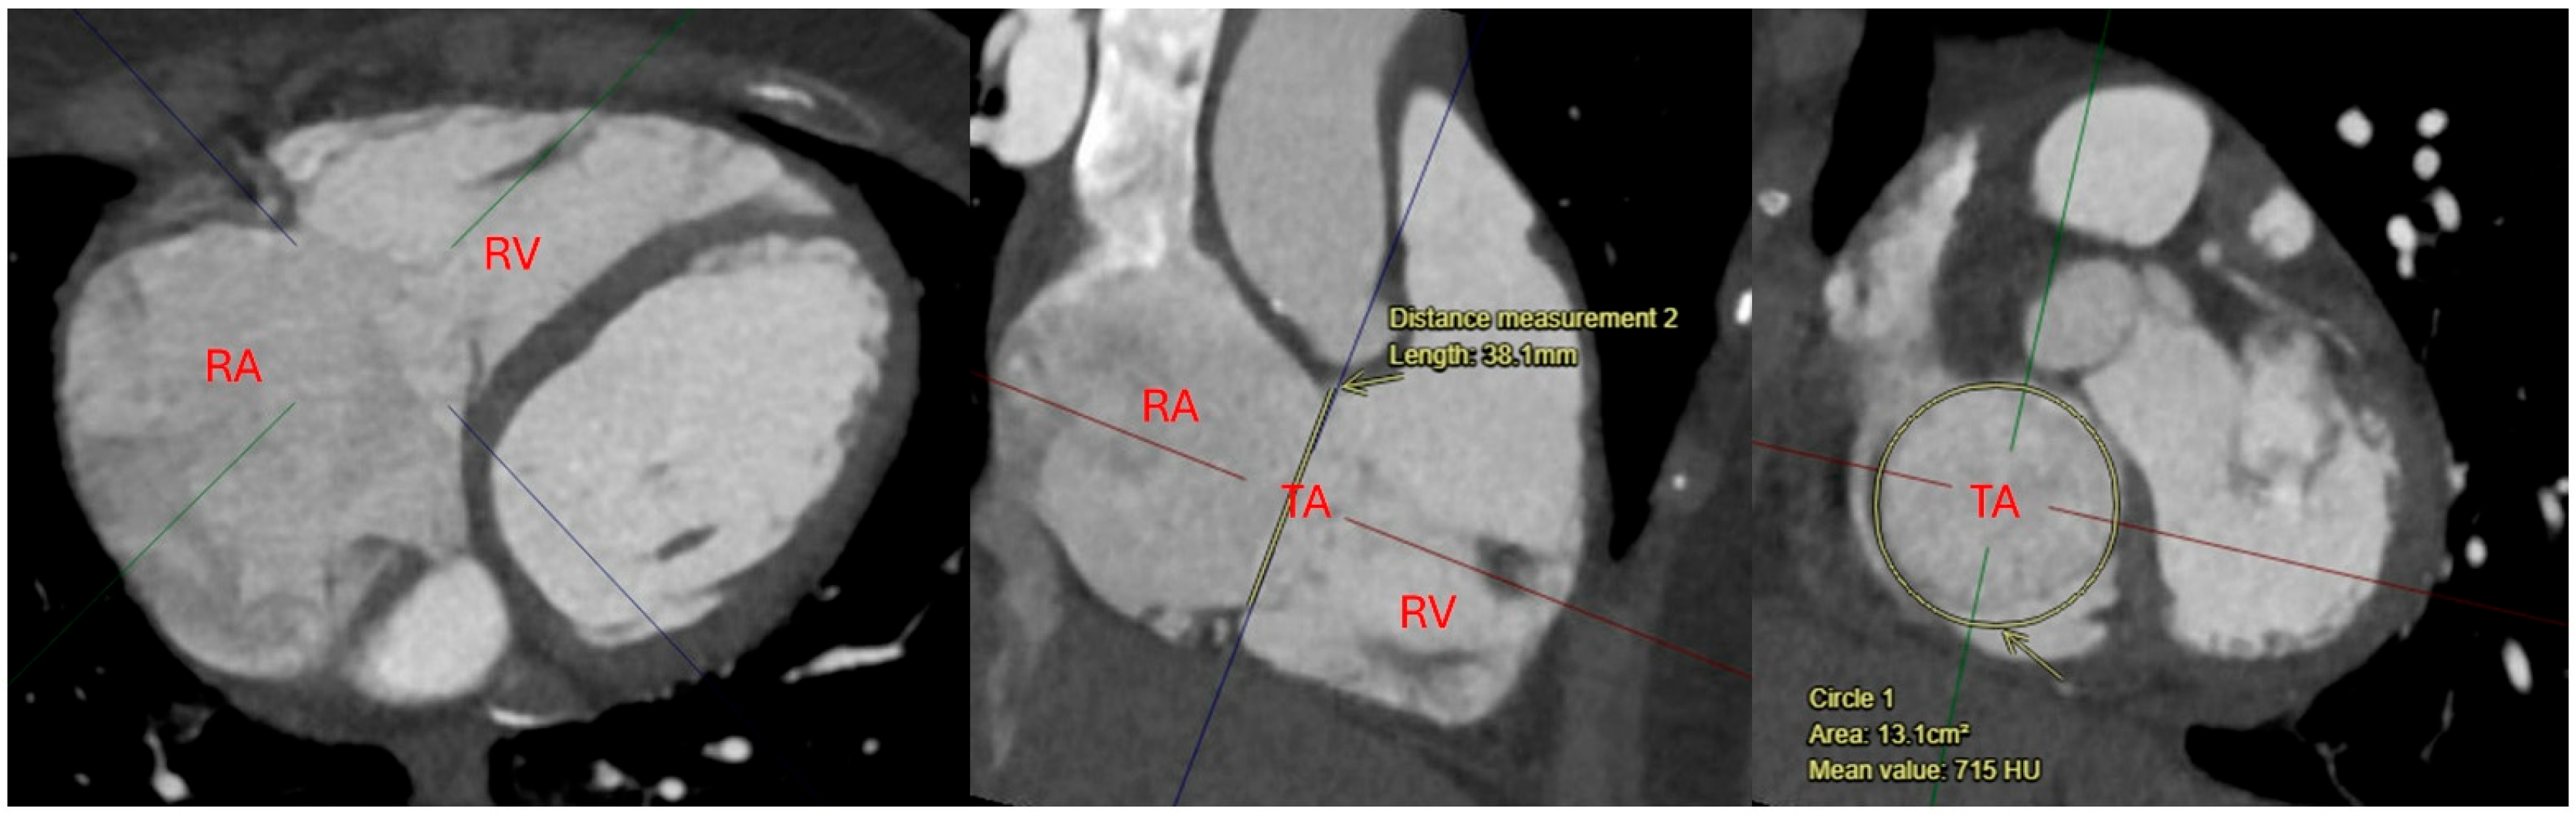

Computed tomography (CT) plays a critical role in preoperative planning for isolated TR before surgical and transcatheter repair approaches. CT provides high-resolution, three-dimensional imaging with detailed anatomical information of the tricuspid valve apparatus and right heart structures throughout the cardiac cycle. This information is essential for assessing valve morphology, annular dimensions, and the spatial relationship of the tricuspid valve to adjacent structures such as the coronary sinus and right coronary artery [32]. For transcatheter interventions, CT is invaluable for determining patient eligibility, guiding device sizing, and identifying potential procedural challenges, such as annular calcification or unfavorable anatomy (Figure 3). CT also provides a tool to assess venous access routes, including the femoral and jugular veins used for transcatheter procedures. In surgical planning, CT aids in visualizing the extent of right atrial and ventricular enlargement, as well as associated pathologies like endocarditis or congenital abnormalities [33]. The combination of anatomical and functional data provided by CT enhances diagnostic accuracy, optimizes patient selection, and improves the safety and efficacy of novel transcatheter therapies for severe TR [32,33].

Figure 3.

4D-CTA MPR image showing tricuspid annulus anatomy measurements Abbreviations: TA: tricuspid annulus; RA: right atrium; RV: right ventricle.

Figure 3—4D-CTA MPR image showing tricuspid annulus anatomy measurements.